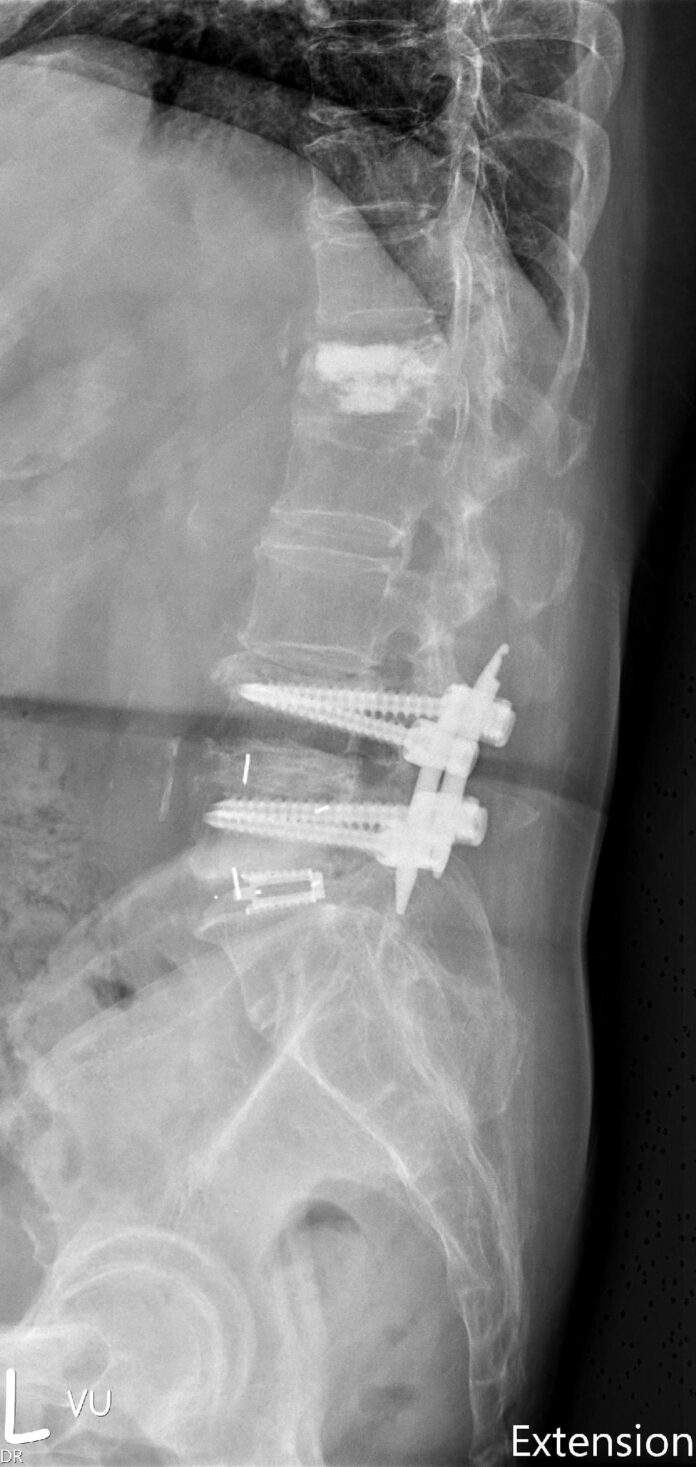

79歲的陳女士,因左下肢麻木且行走困難已數月至門診求診,過去腰椎曾經手術過,影像檢查發現腰椎第四五節椎間融合術後的鄰近節,第五腰椎第一薦椎椎間盤因應力轉移,出現椎間盤空洞化、椎管狹窄及黃韌帶增厚等問題,有鑑於病人主要問題是單節段鄰近節狹窄及椎間高度喪失,且原先植入螺釘並沒有鬆動或失穩需延長固定,因此,陳女士接受微創可撐開式椎間融合術,改善神經痛及跛行的困擾,並縮短了復原時間。

治療選擇方面,傳統翻修(移除舊螺釘並延長內固定或重新固定)通常提供較確實的即時穩定與重建脊椎矢狀面,但伴隨較長手術時間、更多出血、軟組織剝離、感染與新螺釘固定相關併發症。若主要症狀為椎管狹窄及局部椎間高度喪失,後路單獨式可撐開椎間融合器是一個可考慮選項,更適合高齡或不宜大範圍手術的病人群。

陳晉瑋說,可撐開設計的椎間融合器在術中可恢復較大椎間高度與椎間角度(lordosis),有利於解除神經壓迫,但在骨質差或脊椎動態不穩定病人,臨床系列報告顯示單獨式椎間融合器仍有下陷及後移的事件發生,應謹慎評估個案是否符合適應症。